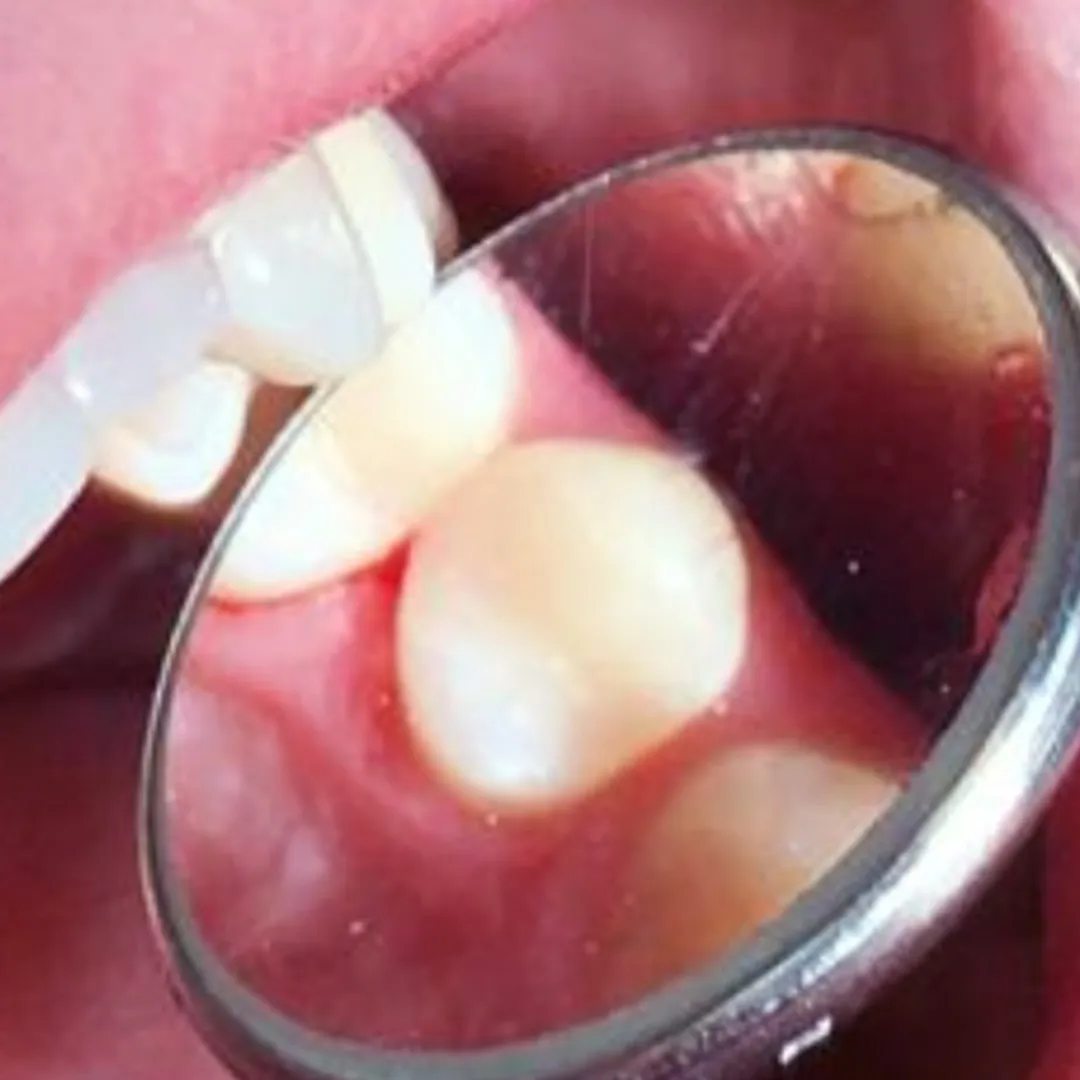

В «Стоматологию Комфорта» обратилась пациентка с жалобами на кратковременные боли от приёма холодных продуктов в области 27 зуба. В ходе осмотра врачом-стоматологом-терапевтом Похилько Н. Г. была обнаружена кариозная полость на жевательной поверхности 27 зуба. Зондирование было болезненно, перкуссия не вызвала реакции. Похилько Н. Г. провела ревизию и обработку полости под контролем кариес-маркера. Был поставлен диагноз: хронический глубокий кариес 27 зуба окклюзионно. Врач принял решение о лечении кариеса с установкой пломбы из материала Estelite.

- постановка пломбы из композита Estelite;

- шлифовка и полировка пломбы;